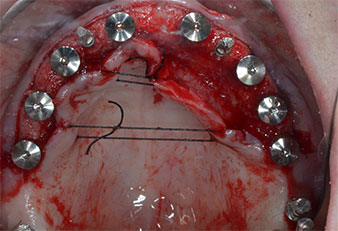

Three years later it was time for a maxillary denture of the same type. Based on CBCT planning sinus augmentation was avoided with the aid of short implants, and a surgical template was used to transfer the planned positions to the alveolar ridge (Figs. 1 and 2).

A flame-shaped, diamond-coated piezoelectric instrument (Piezomed I1) was used to mark the implant positions and to perform pilot preparation (Fig. 3). Care was taken to use an up and down movement, with reduced power, full irrigation and low pressure (below 300 g). Next a pilot instrument (Piezomed I2A/I2P) was applied for the initial 2 mm diameter enlargement of the implant sites (Fig. 4), followed by a 3 mm insert (Fig. 5).

Due to the relatively hard bone (D2) in this area, the 10 mm long implant sites at positions 11 and 21 were finalized with a 4 mm diameter rotary drill, in combination with a W&H WS-75 L surgical contra-angle handpiece, the W&H Implantmed implant motor and the optional W&H Osstell ISQ module. In contrast, due to the soft bone the posterior sites were prepared to a final 3 mm diameter using the Piezomed I3P instrument. The implants were finally placed transgingivally to osseointegrate for three months (Figs. 6-10). The existing denture was retained on four provisional implants (Fig. 8).